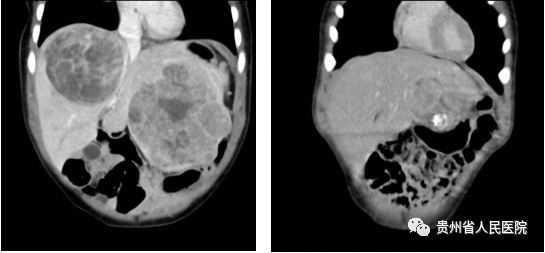

近日,上海儿童医学中心贵州医院、贵州省人民医院小儿外科普胸团队成功为一名两岁的患儿进行了复杂肝母细胞瘤微创切除手术,术后患儿康复良好 2022年12月初,两岁的小瑞(化名)因其父母无意间发现其腹部包块前来就医,完善腹部CT显示小瑞肝脏左叶及右叶各有一个包块,约“柚子”大小(图1左)。

患儿影像学检查,左:术前提示肝脏左、右叶巨大占位 右:化疗四个疗程后肝脏左、右叶占位体积明显减小 面对难点,小儿外科普胸团队利用远程会诊与上海儿童医学中心进行了MDT讨论,经讨论后拟定先行术前化疗方案,待肝脏包块体积缩小后再行手术切除的治疗。

今年1月至3月期间患儿顺利完成四个疗程化疗,化疗后评估肝左、右叶包块体积明显减小,约“橘子”大小,已具备手术切除条件(图1右)手术前小儿外科、肝胆外科、麻醉科、放射科、PICU进行了MDT讨论,决定在腹腔镜下行肝脏右前叶切除和左外叶部分切除术。